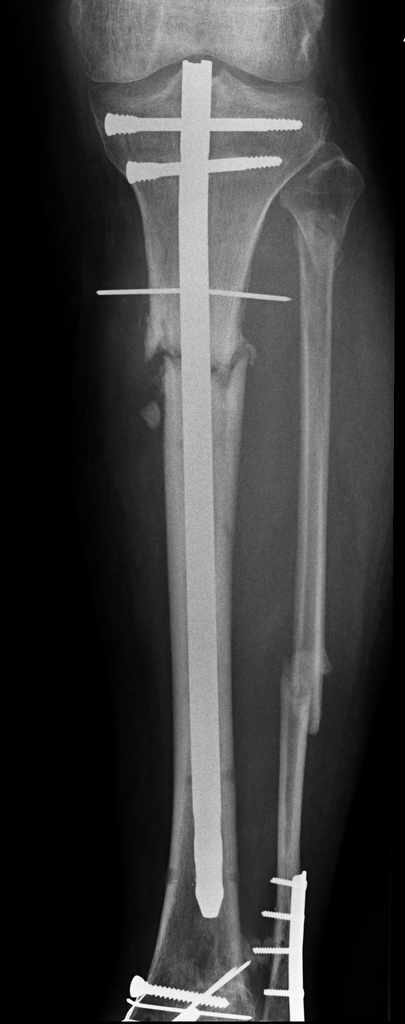

У пациента 55 лет после открытого перелома костей голени остро развилось глубокое нагноение

верхней трети голени.

Травма в октябре 2007 года открытый перелом 3 ст - ПХО, наложение стержневого аппарата,

остеосинтез ложыжек при поступлении. После заживления ран через 10 дней - закрытый

интрамедуллярный остеосинтез без рассверливания. Применялась отклоняющая спица,

которая оставлена подкожно для контроля положения проксимального фрагмента. Певичное

заживление ран. Динамизация остеосинтеза через 1,5 месяцев, однако в динамике

рентгенологически - признаки формирования ложного сустава. Последние 2 месяца ходьба с

полной нагрузкой без клинических жалоб. 5 дней назад без видимой причины подъем

температуры, гиперемия по внутренней поверхности в/3 голени, формирование абсцесса. При

вскрытии 2 дня назад около 80 мл сливкообразного гноя. Спица удалена (видимо она и была

причиной инфицирования), винты нестабильны - также удалены. Гвоздь оставили на месте

(пока). Дном гнойной раны явлется кость, зонд доходит до гвоздя. в настоящее вроем рана

дренируется выпускниками, количество отделяемого уменьшается. Вопрос по дальнейшему

лечению. Интрамедуллярная фиксация оказалась нестабильной, поэтому рассматриваем 2

варианта: 1. Удаление стержня - переход на ВКДО по Илизарову с промывным дренированием

канала. 2. То же, но вместо промывания - интрамедуллярный тонкий стержень с антибиотиком на

цементе. Просьба откликнуться имеющих личный опыт лечения таких осложнений относительно

нюансов, и возможно других вариантов.